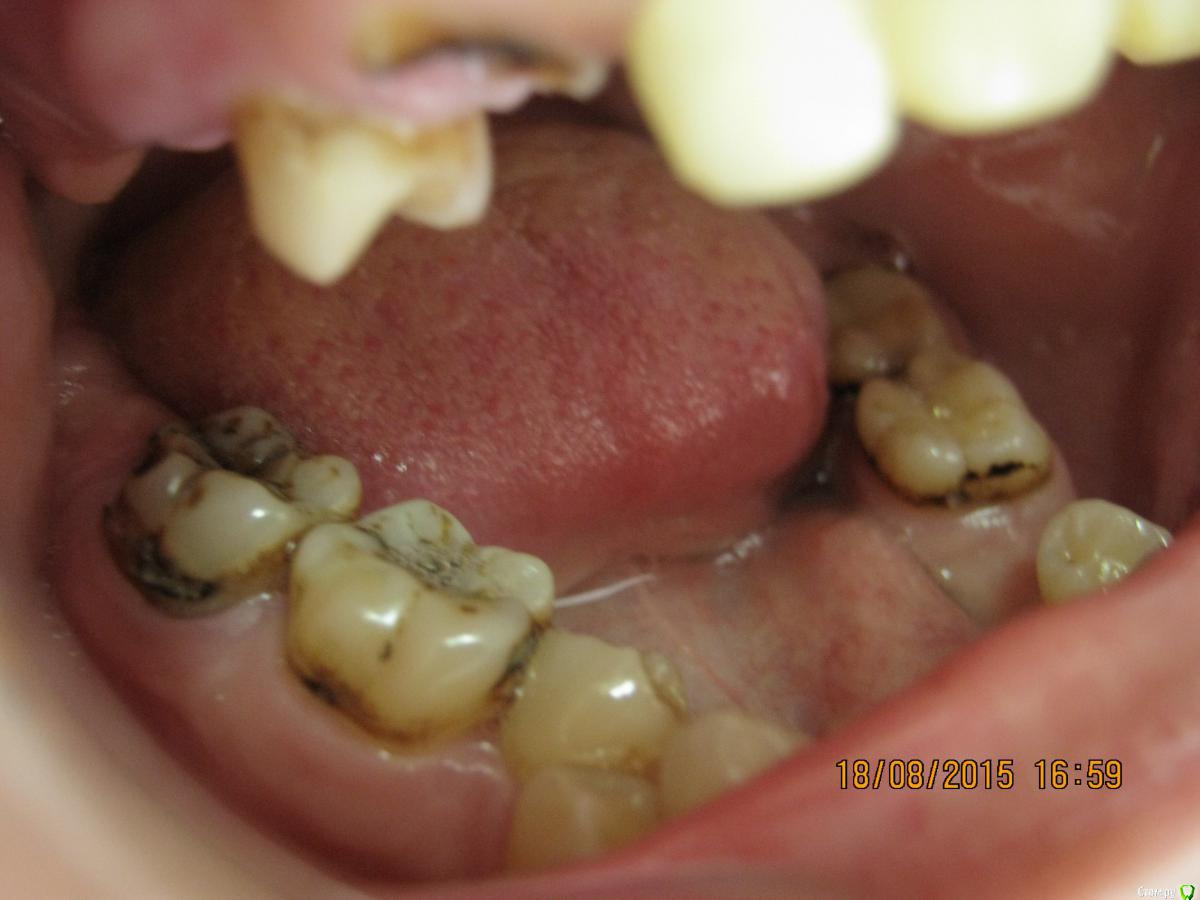

SeregaStomatolog Опубликовано 18 августа, 2015 Поделиться Опубликовано 18 августа, 2015 Добрый вечер уважаемые коллеги!В клинику обратилась пациентка с такой ситуацией во рту.Подскажите пожалуйста что можно сделать и с чего начать. Ссылка на комментарий

SeregaStomatolog Опубликовано 18 августа, 2015 Автор Поделиться Опубликовано 18 августа, 2015 Во-первых она хочет нормально улыбаться,не стесняясь отсутствующего клыка.Во-вторых она хочет нормально жевать,т.к. отсутствие 1.7,1.6 не позволяет это делать.Я сразу сказал пациентке что вариантов без ортодонтии мало (если они вообще есть) и обещать ничего не стал.Случай сложный,поэтому хочется узнать в принципе,на будущее,какие варианты лечения возможны (если можно по подробнее).Пока что я снял слепки,отлил модели-пошел за советом к коллегам в другую клинику-все настаивают на ортодонтии.Теперь вся надежда на Вас коллеги,подскажите что можно придумать более менее приемлемое без ортодонтии. Ссылка на комментарий

SeregaStomatolog Опубликовано 18 августа, 2015 Автор Поделиться Опубликовано 18 августа, 2015 Сделав как хочет пациентка вы не получите красивый результат, которого она ждет! и получится что вы не смогли реализовать ее мечты , а значит доктор неахти)) да и вы не особо результатом будете довольны, вам это надо? Если в эстетике проблем нет, восстановите функцию. Ненужное удалить, длинные зубы дэпульпировать, укоротить ну и коронуйте))Мне кажется если я возьмусь,то все равно не буду результатом доволен,т.к. все реализовать не получится.Самая большая проблема в области отсутствующих 1.6,1.7-зубо-альвеолярное удлинение 4.6,4.7 настолько велико,что они практически касаются слизистой в области 1.6,1.7. Ссылка на комментарий